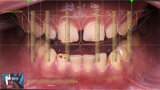

Kdo potřebuje Digital Smile Design (DSD)?